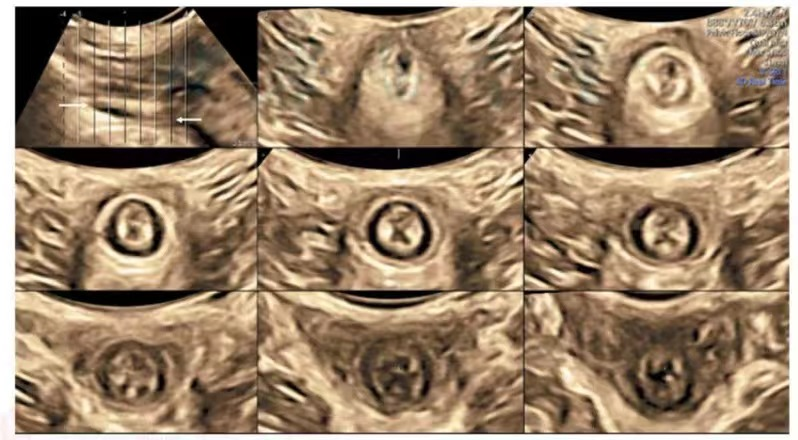

进行康复治疗前要做什么检查?首选超声检查现在临床上评估盆底功能障碍性疾病最好的影像学方法是实时三维(俗称四维)盆底超声检查,超声可以简单、方便、无创、实时、动态的观察盆腔的情况,我院超声医学科是目前河源市率先开展盆底实时三维的科室,实时三维盆底超声弥补了普通二维超声不能检查出的横断面的扫查,可以检查出膀胱膨出、尿道膨出、子宫脱垂、阴道穹隆膨出、直肠膨出、会阴体组织缺陷;并且可以应用TUI技术(类似于CT的断层扫查)、容积成像检查肛提肌是否有撕裂、肛门括约肌是否有撕裂、测量肛提肌裂孔面积。

TUI模式:缩肛状态下观察肛体肌的连续性图片来源:盆底超声检查中国专家共识2022版

TUI模式:缩肛状态下观察肛门括约肌的连续性图片来源:盆底超声检查中国专家共识2022版